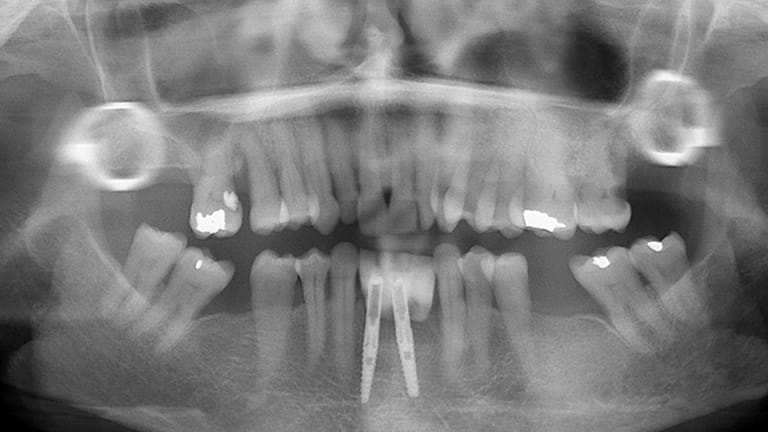

Implant Bridge

Implant Denture

Implant Full Arch

Below is a few examples of what DENTAL IMPLANTS can do for you and your smile!